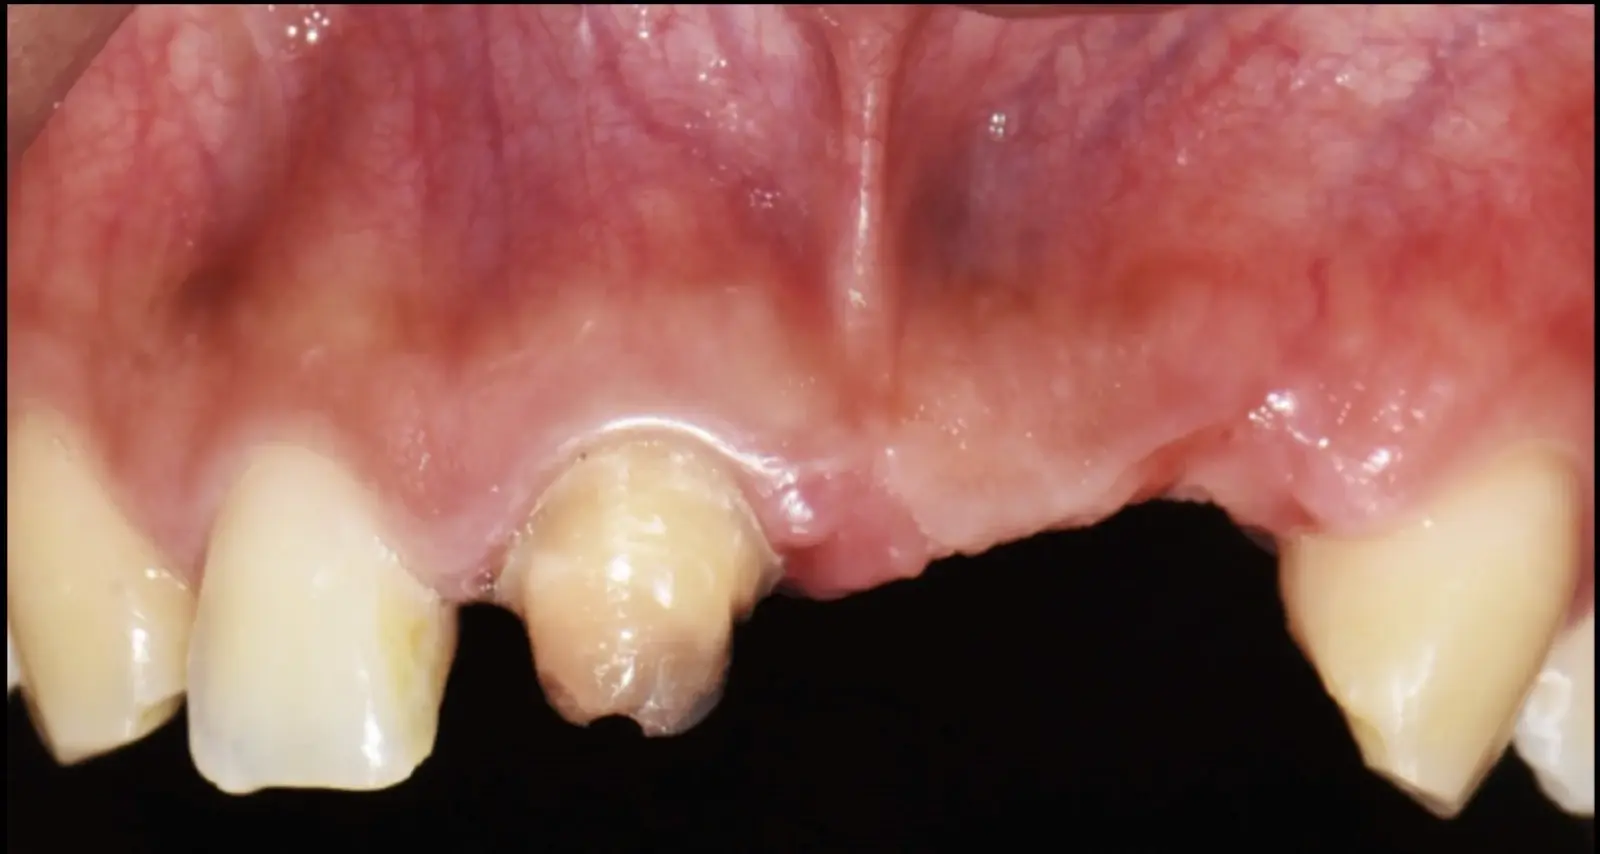

Los casos clínicos que presentamos a continuación muestran claramente las ventajas del piezoeléctrico en diversos procedimientos de terapia ósea regenerativa. En el primer ejemplo, una reconstrucción de reborde con injertos en bloque previo a la planificación de implantes dentales en un caso de edentulismo total superior con una severa reabsorción ósea. En el segundo ejemplo se utilizó esta tecnología para la reconstrucción de lechos para implantes de estructuras óseas con hueso en bloque de origen bovino y posteriormente la colocación de implantes dentales. Los dos casos son parte del capítulo 9 del libro “Cirugía piezoeléctrica: generalidades y aplicaciones clínicas”.